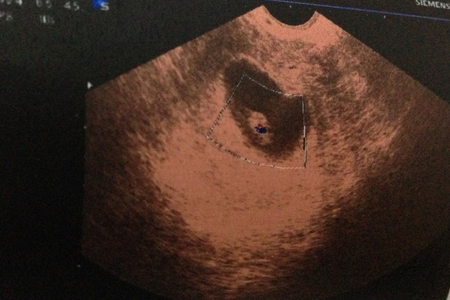

受精是精子穿入卵子形成受精卵的过程。受精一般发生在排卵后的12小时之内的输卵管壶腹部,整个受精过程大约需要24小时。

在千山万水人海相遇,原来你也在这里。发育正常并已获能的精子与发育正常的卵细胞在限定时间内相遇是受精的前提条件。